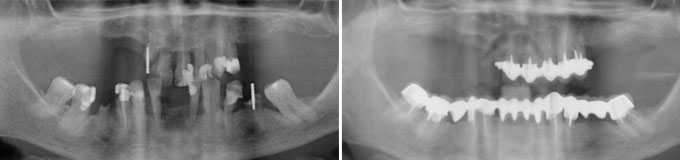

J’ai de vieux bridges à refaire et je veux autre chose.

Solution : on les remplace par la mise en place de plusieurs implants

Un grand bridge supérieur à refaire, le patient veut des dents individuelles.

J’ai un appareil amovible du bas que je ne supporte plus, je veux des dents fixées.

Solution : on rajoute autant d’implants que il manque des dents qui serviront à fixer vos nouvelles couronnes.

Mon appareil du haut va bien, mais je voudrais supprimer l’appareil du bas.

Dans ce cas, la prothèse amovible inférieure est supprimée, remplacée par un bridge fixe de 10 dents.